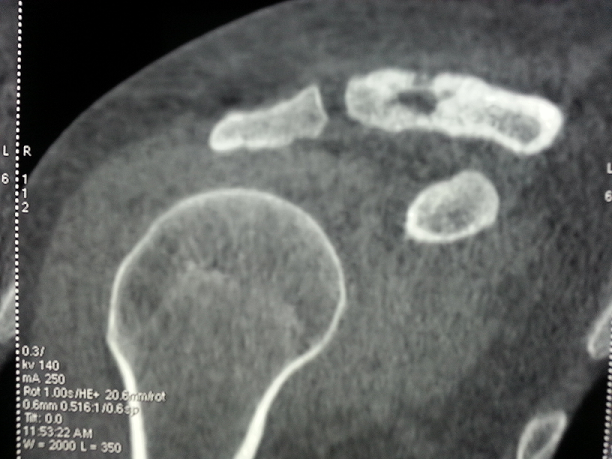

Il s'agit Mme S.S âgée de 30 ans et sans antécédents pathologiques particuliers. L'anamnèse a retrouvé la notion de consommation occasionnelle de produits laitiers non pasteurisés. Elle a consulté suite à la découverte fortuite d'une tuméfaction en regard de la clavicule droite, sans signes généraux associés. A l'examen, il s'agit d'une formation de 4 cm de grand axe, de consistance dure, indolore, sans signes inflammatoires en regard et fixe par rapport au plan profond. Le reste de l'examen somatique était normal. La biologie était sans anomalies. L'IDR à la tuberculine était phlycténulaire. La radiographie standard de l'épaule a montré une lacune osseuse du bord distal de la clavicule droite. L'IRM a objectivé une ostéolyse cortico-médullaire antéro-supérieure de la clavicule droite avec un aspect irrégulier, érodé et aminci de la corticale adjacente, épargnant l'articulation acromio-claviculaire ainsi qu'une inflammation des parties molles péri-osseuses prédominante en antérieur. La biopsie osseuse a montré de multiples lésions folliculaires faites de cellules épithélioïdes et de cellules géantes entourant de larges plages de nécrose caséeuses. Le scanner thoraco-abdomno-pelvien et la scintigraphie osseuses n'ont pas trouvé d'autres atteintes. Le diagnostic d'une tuberculose claviculaire isolée était alors retenu. La patiente était mise sous traitement antituberculeux quadruple (izoniazide, rifampicine, éthambutol et pyrazinamide) pendant deux mois puis une bithérapie (izoniazide et rifampicine) pour une durée totale de traitement de 9 mois. L'évolution clinique et radiologique était favorable. Le recul est de 18 mois.